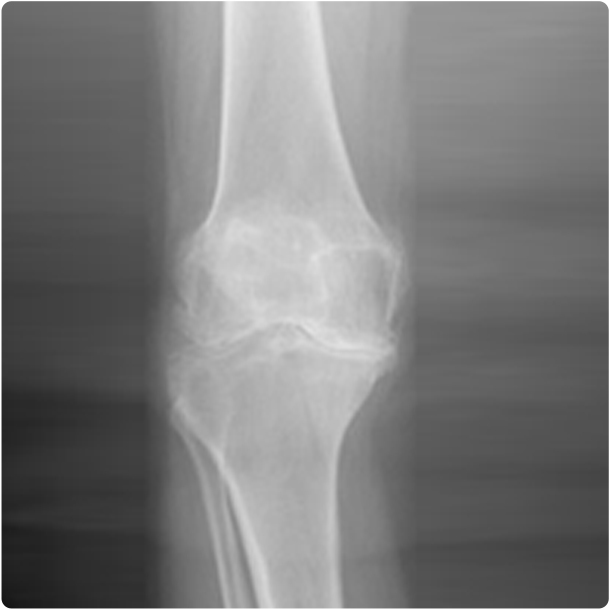

Diz Artroskopisi

Diz eklemi artroskopinin en yaygın kullanıldığı eklemdir. Diz içindeki tüm sorunların tanı ve tedavisinde son derece etkili bir yöntemdir. Ameliyat edilen hastaların büyük bir kısmı aynı gün ya da bir gün sonra taburcu edilebilmekte ve kısa bir süre içinde normal yaşamlarına dönebilmektedirler.

Diz artroskopisi ile tedavi edilebilen sorunlar şunlardır:

1. Menisküs yırtıkları

2. Ön ve arka çapraz bağ yırtıkları

3. Kıkırdak hasarları ve çocuklarda kıkırdak ayrılması

4. Osteoartrit (kireçlenme)

5. Romatolojik hastalıklar

6. Diz eklemi içi kırıkların bazıları

7. Eklem faresi (kıkırdak kemik parçanın eklem içinde serbest dolaşması)

8. Plika sendromu ve diz içi yapışıklıkları

9. Bazı diz içi tümörler

10. Patella (diz kapağı kemiği) çıkık ve yarı çıkıkları